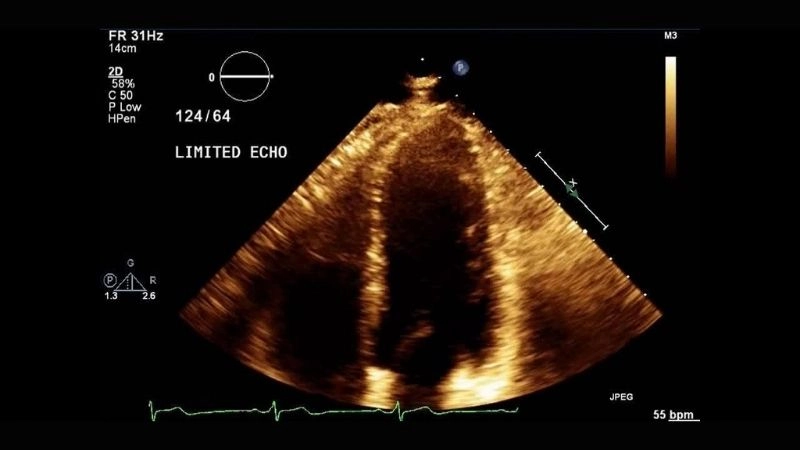

Images visual examples of Coronary Artery Spasm (Prinzmetal's Angina)

Coronary artery spasm occurs when a coronary artery temporarily tightens, restricting blood flow to the heart. This can cause chest pain, ECG changes, and sometimes arrhythmias, highlighting the importance of timely diagnosis and lifestyle modifications.